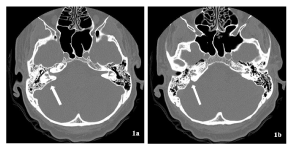

At the age of 37 the Patient (Pt) presented a sudden headache and then a stiffness of the nuchal region after a trivial neglected right otitis media. A post-traumatic pathological pathway between middle ear and the posterior cranial fossa was evidenced with a urgent CT (Figure 1). The new otogenic meningitis was confirmed with a MRI (Figure 2), wich showed an abscess of the brainstem. This infection has regressed thanks to medical therapy alone.

Figure 1. Pre-surgery CT without contrast: post-traumatic pathological pathway between middle ear (in front of the oval window), inner ear and posterior right cranial fossa. Look at arrows to see the transverse petrous temporal bone fracture.